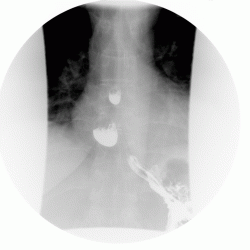

Пищевод.

дивертикулы пищевода

Изображение Изображение